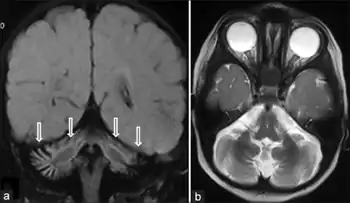

SIL1-negative Marinesco-Sjögren syndrome a,b) MRI coronal and axial image shows cerebellar vermian and hemispheric atrophy | |

Diagnosis of MSS is based on clinical symptoms, magnetic resonance imaging (MRI) of the brain (cerebellar atrophy particularly involving the cerebellar vermis), and muscle biopsy.